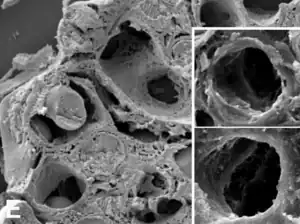

- Un capilar sanguíneo es un vaso de diámetro entre 8 y 12 µm. Su pared está formada por una sola capa de células endoteliales y recibe pasivamente el flujo vascular que le llega.

- Una vénula es un vaso con un diámetro entre 15 y 100 µm. Su pared no tiene fibras elásticas ni células de músculo liso y se dilatan fácilmente.